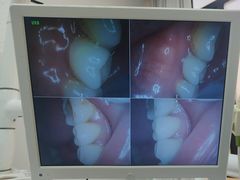

• 牙博士口腔品牌连锁(杨浦店)

• -牙博士口腔品牌连锁(杨浦店)